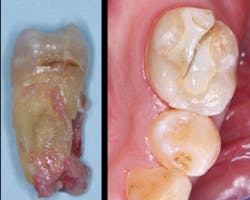

It is well known that all people perceive pain differently. Until you know the pain threshold of a specific patient, you cannot decide what level of analgesic to prescribe. The patient shown in Figures 1 and 2 had only an occasional awareness that there was movement in the grossly diseased mandibular molar tooth, while the patient with radiographically adequate endodontic treatment on a lower molar shown in Figure 3 was in constant pain, which interfered with his daily work. Pain threshold is obviously different from patient to patient. Dentists soon learn the pain thresholds of their patients.

Figure 1: Mandibular molar of a patient who was aware of movement but who tolerated the mild discomfort for many months before seeking treatment

Figure 2: The molar shown in Figure 1 had obviously been in a state of degeneration for many months, but the patient did not have any significant disability related to the tooth. This patient had an extremely high pain threshold.

Pain threshold is defined as the least stimulus intensity at which a patient perceives pain. Every dentist knows that it varies hugely. What is mild pain to one patient can be severe pain to another.